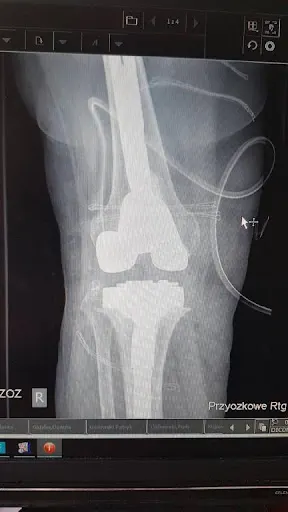

### Przychodnia Ortopeda w Gdyni W Gdyni, przy ulicy Sojowej 33a (81-589 Gdynia, Polska), działa przychodnia lekarska Ortopeda. Placówka ta skupia się na opiece specjalistycznej w dziedzinie ortopedii, oferując konsultacje i usługi medyczne związane z układem ruchu. Znajduje się w dogodnej części miasta, co ułatwia dostęp mieszkańcom Trójmiasta poszukującym pomocy w zakresie schorzeń stawów, kości czy urazów. Adres Sojowa 33a to miejsce, gdzie pacjenci mogą skorzystać z podstawowej diagnostyki i leczenia w ramach przychodni lekarskiej. Przychodnia Ortopeda funkcjonuje jako lokalna placówka medyczna, wpisując się w sieć usług zdrowotnych dostępnych w Gdyni. Pacjenci zapisywani są na wizyty ortopedyczne, a personel zajmuje się typowymi problemami ortopedycznymi spotykanymi w codziennej praktyce. Lokalizacja w Gdyni pozwala na szybki dojazd komunikacją miejską lub samochodem, co jest praktyczne dla osób z okolicy. Choć przychodnia nie posiada jeszcze opinii na platformach takich jak Google, stanowi opcję dla tych, którzy szukają specjalistycznej opieki ortopedycznej w swoim mieście. Warto sprawdzić aktualne godziny przyjęć bezpośrednio w placówce pod podanym adresem. (Słowa: 178)